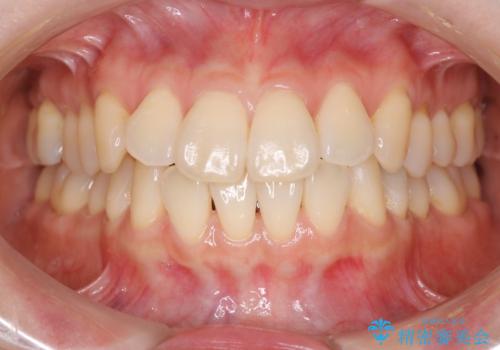

【非抜歯】インビザラインで正しい噛み合わせを

【非抜歯】インビザラインでガタつきと口元を改善!非抜歯でも印象が変わる矯正治療